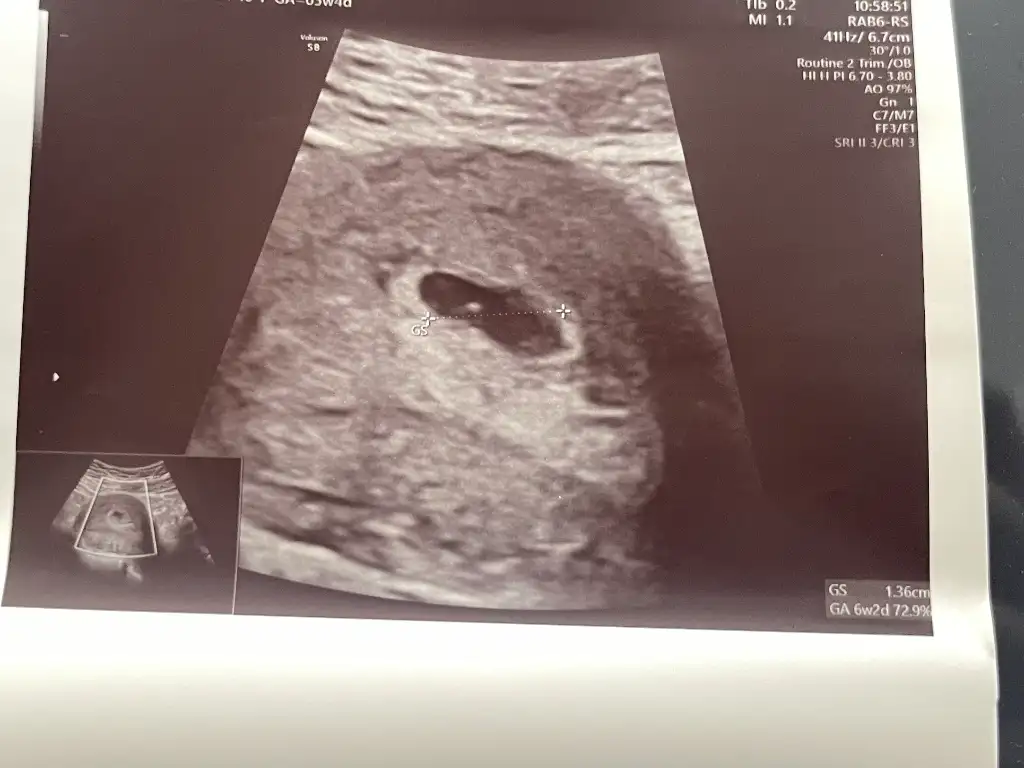

Erkek bencemerhaba 11+6 haftalık ilk ve son karından ultrason fotoğraflarını ekledim rica etsem bakabilir misiniz

Oğlumun kesesıne benzıyor..Sağlıkla gelsinmerhaba 11+6 haftalık ilk ve son karından ultrason fotoğraflarını ekledim rica etsem bakabilir misiniz

merhabalar evet erkekmiş teşekkür ederim insallahOğlumun kesesıne benzıyor..Sağlıkla gelsin